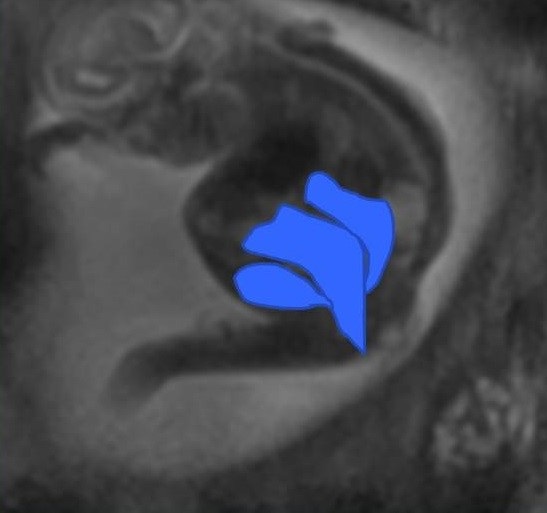

Figure 4

Fetal MRI of a 22 week fetus with a cloaca, and the bladder, vagina and rectum are highlighted in blue.